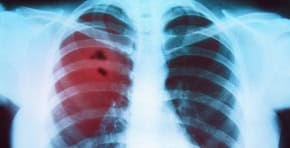

Lung Cancer

If you’re a smoker over 50, OncoSure may detect early signs, even before changes appear on scans.